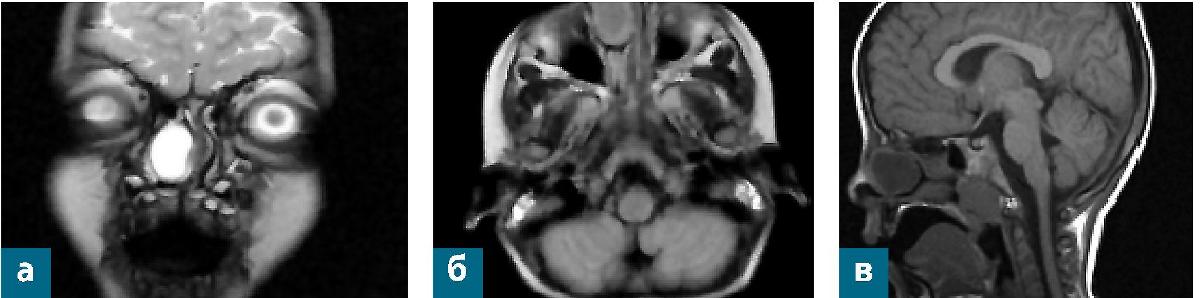

Затем ребенок находился под наблюдением у врача-оториноларинголога по месту жительства, в динамике отмечался медленный рост образования наружного носа и пульсация. При выполнении УЗИ мягких тканей носа в параорбиталь-ной области справа визуализируется опухолевидное образование мягко-эластичной консистенции, безболезненное, кожа над ним не изменена, размеры около 15 x 14 мм. Заключение УЗИ: УЗ-признаки кистозного вида солидного включения с гетерогенным аваскулярным содержимым, размеры 15 х 14 х 7,6 мм. В 6 мес пациентке была проведена операция в частном центре. Со слов матери, патоморфологического заключения в бумажном виде не выдали на руки, сообщили посредством телефонной связи, что по гистологическому исследованию верифицирована фиброма наружного носа. Через полгода после первого хирургического лечения родители стали отмечать увеличение образования и возобновление жалоб на затруднение носового дыхания. Выполнены МРТ ГМ и КТ ОНП в условиях общей анестезии. На компьютерной томограмме ОНП выявлены кт-признаки костного дефекта носовых костей (область переносицы) с наличием капсульного кистозного образования, с пролабированием в правый носовой ход и значительной деформацией носовой перегородки, дифференцировать с эпидермальной кистой. Минимальные катаральные изменения единичных передних этмоидальных клеток слева. Аденоиды 2-3 степени (рис. 2).

Рис. 2. Компьютерная томограмма ОНП пациентки К. до хирургического лечения: а - коронарная проекция; б - аксиальная проекция; в - 3D-реконструкция

По данным МРТ головного мозга выявлены признаки кистозного образования полости носа и ОНП справа (рис. 3).

Рис. 3. МРТ ГМ пациентки К. на догоспитальном этапе: а - коронарная проекция; б - аксиальная проекция; в - сагиттальная проекция